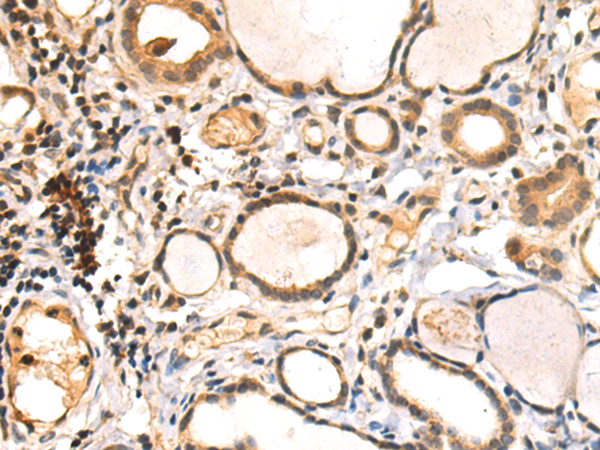

分类: 科研抗体货号: P06877别名: HD7; HD9; HD7b; HDAC; HDRP; MITR; HDAC7; HDAC7B; HDAC9B; HDAC9FL应用: IHC反应种属: Human, Mouse